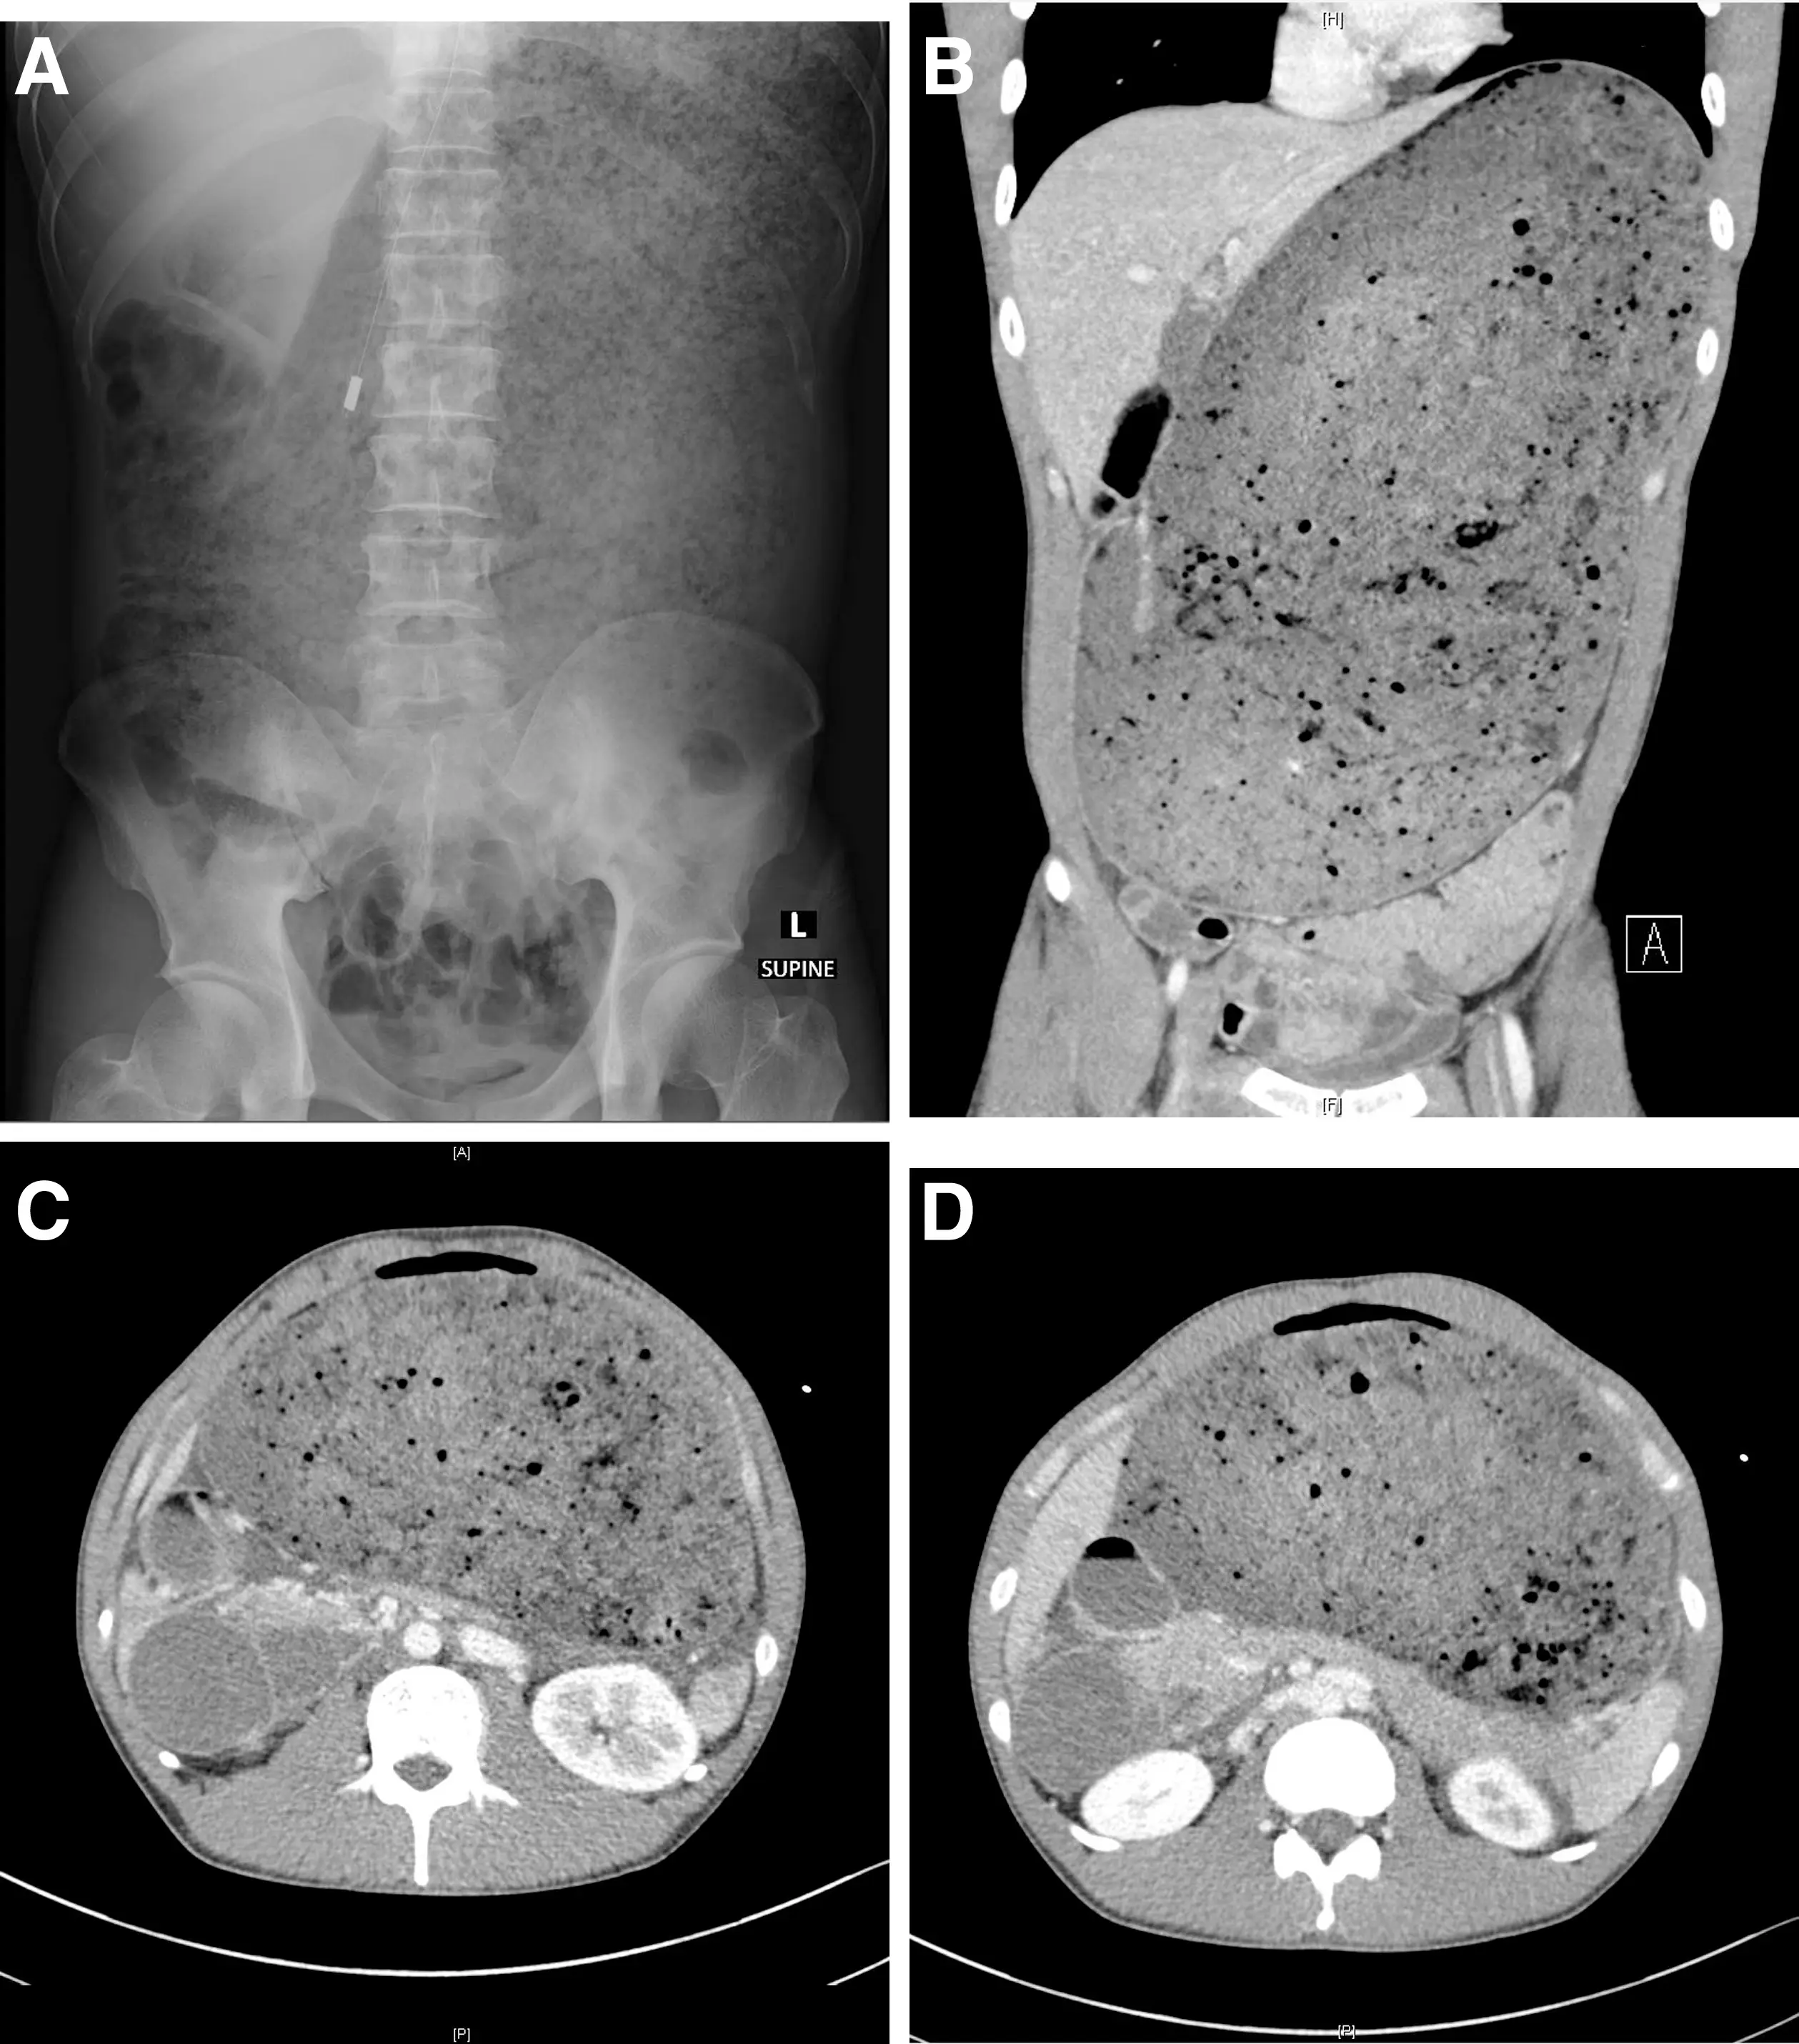

According to the report, published in Gastroenterology aga (American Gastroenterological Association), the man underwent a computed tomography scan of the abdomen and pelvis which detailed the severity of his swollen belly.

It showed his stomach and part of his small intestine were 'grossly distended with food material', as well as an abrupt narrowing in another part of the small intestine.

Meanwhile, 'the pancreas was compressed' and the bowels were pushed down.